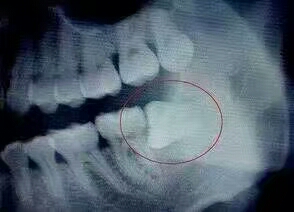

1、阻生智齿

阻生齿是指因为生长的位置不当,导致不能萌出到正常咬合位置的牙齿。因此阻生智齿,通俗点来说,就是“阻碍生长的智齿”,是指因为软组织问题或颌骨骨量不足,智齿不能正常萌出,被牙龈或牙槽骨包裹在里面,经常引发炎症、疼痛。

一般我们说牙疼拔智齿,很多就是阻生智齿,因为大部分甚至全部都埋伏在颌骨中,拔除的难度也比较大,需要削掉一部分颌骨,再将智齿切碎取出,如下图: